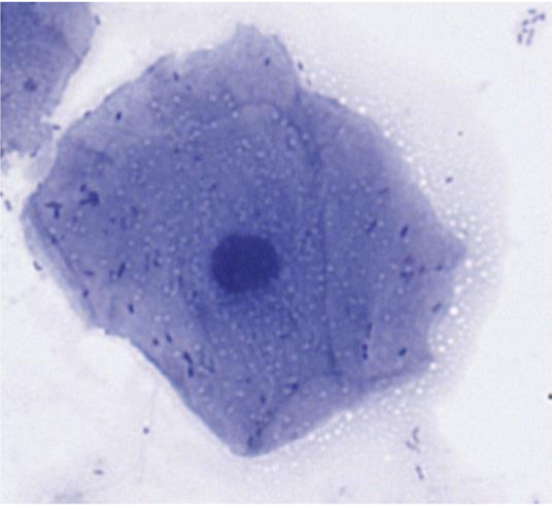

Kantig och tunn cell med pyknotisk kärna

Superficialcell